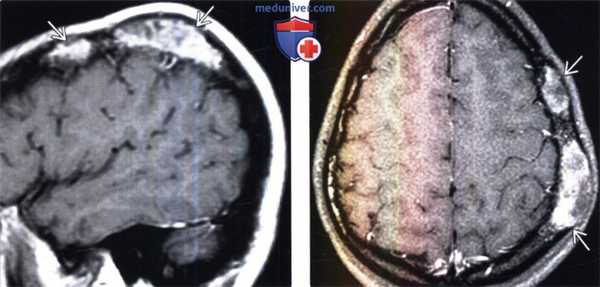

(Слева) При КТ в костном окне в аксиальной проекции отмечаются утолщение, склероз и изменения типа матового стекла левого большого крыла клиновидной кости. Обратите внимание на левый клиновидно-височный шов, резко разграничивающий нормальную кость и зону патологических изменений; такая картина типична для фиброзной дисплазии.

(Справа) При аксиальной MPT Т2ВИ FS у этого же пациента в зоне патологических изменений кости регистрируется преимущественно гипоинтенсивный сигнал. При МРТ отмечается высокая вариабельность МР-сигнала и характера контрастирования пораженной кости, зависящих от соотношения фиброзной и склеротической тканей.